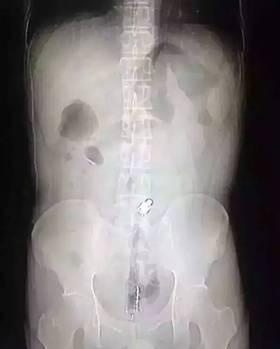

“因?yàn)槲矬w邊緣比較光滑,手術(shù)的時(shí)候,我們兩個(gè)人合作,一個(gè)人順著肚子一點(diǎn)點(diǎn)推,推到肛門口,我把異物拿了出來,大概花了十分鐘時(shí)間!庇舴逭f,這名男子運(yùn)氣算好的,因?yàn)楦鶕?jù)拍片檢查,當(dāng)時(shí)那根振動棒已經(jīng)擠到了肚臍的部位,情況其實(shí)已經(jīng)相當(dāng)危險(xiǎn)。醫(yī)生提醒 “那根振動棒有20公分,人的直腸只有18公分,它的長度已經(jīng)超過直腸了,到達(dá)乙狀結(jié)腸,會引起腸子破裂壞死,如果破了就會有生命危險(xiǎn) 。 ”